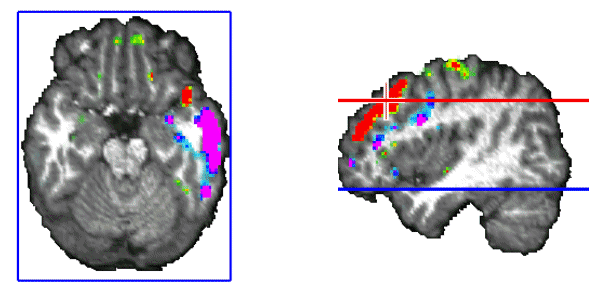

Figure 11. Simultaneous cortical and subcortical activity (amygdala/hippocampus formation) is observed during the interspindles interval.